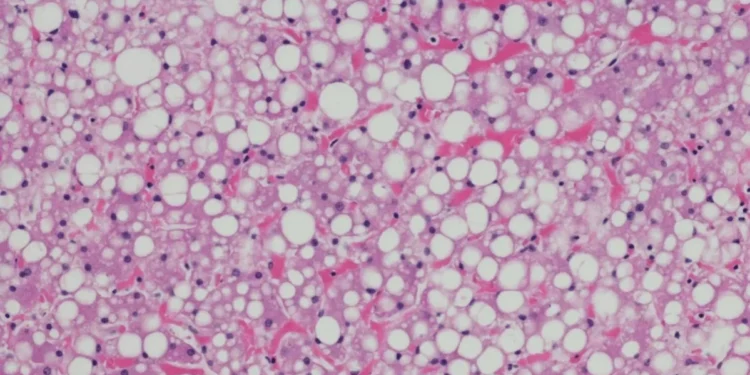

A esteatose hepática é o acúmulo de gordura no fígado que pode, com o passar do tempo, causar uma inflamação crônica e danos no tecido hepático. Normalmente é uma situação benigna mas, sem cuidados, sua evolução pode induzir à fibrose do fígado (substituição das células normais do fígado por tecido fibroso) e até evoluir para cirrose, inclusive com aumento de risco de câncer. Estima-se que o problema atinja ao menos 25% da população adulta – na amostra avaliada a esteatose estava presente em 35,5% dos voluntários.

- Popularmente chamada de gordura no fígado, a esteatose hepática acontece quando as células do órgão acumulam gordura em excesso.